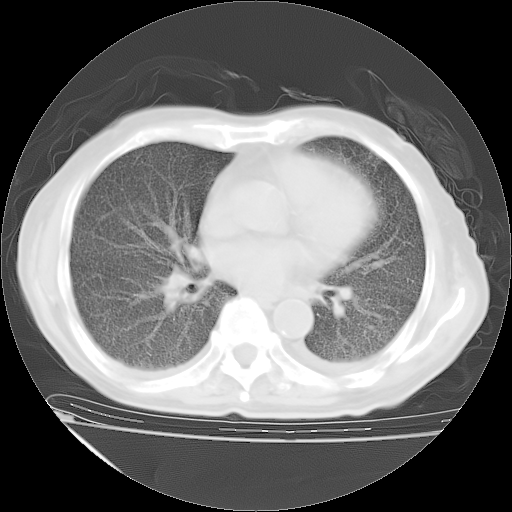

甲强龙80mg/日+抗结核治疗(异烟肼+利福霉素+乙胺丁醇)10天。复查肺部CT。

治疗10天肺部CT